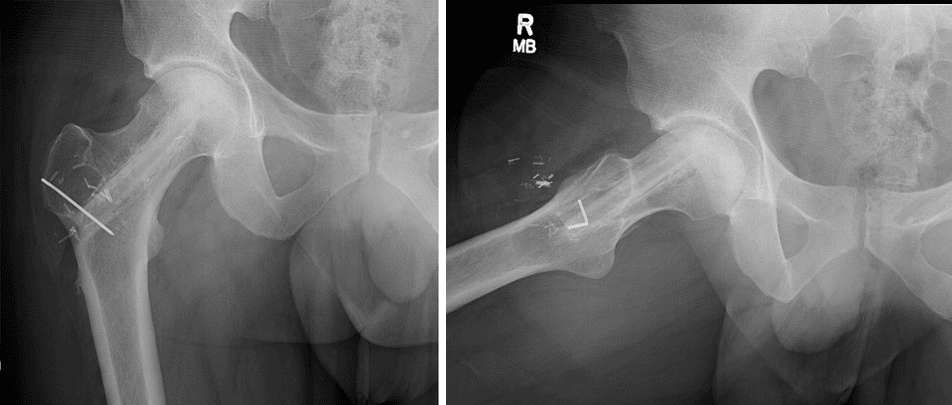

Normal hip and hip with osteonecrosis

(Left) An X-ray of a healthy hip joint. (Right)  In this X-ray, the osteonecrosis has progressed to collapse of the femoral head.

Osteonecrosis is typically seen as a wedge-shaped area with a dense whitish sclerotic (hardened) border in the superior lateral portion of the femoral head. On the lateral view, a line called a “crescent sign” can often be seen just below the surface of the femoral head.

Osteonecrosis of the hip

(Left) This X-ray shows osteonecrosis of the hip. (Right) When viewed close up, the X-ray reveals the “crescent sign” that is typically seen before collapse of the femoral head.

Images courtesy of Stuart J. Fischer, MD, FAAOS